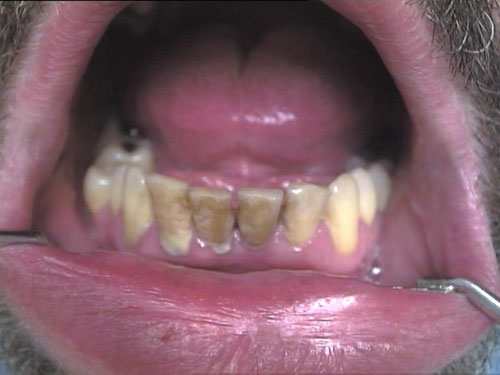

Zahnprothese mit Klammer